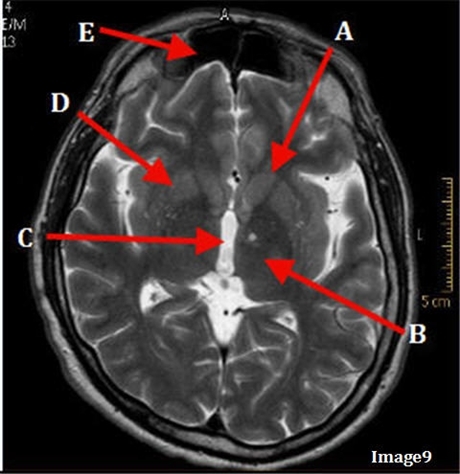

T2 Axial

A

Caudate Nucleus

B

Thalamus

C

Third ventricle

D

Lentiform Nucleus

E

Frontal Sinus